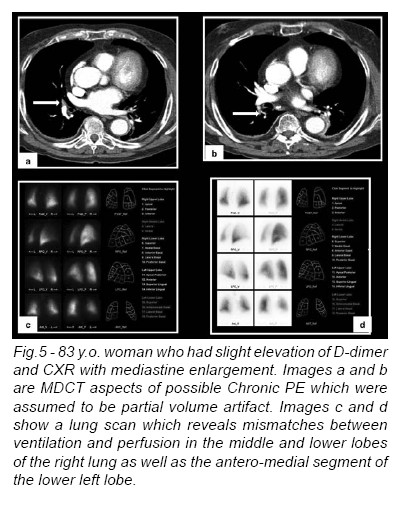

LUNG SCANNING (1,2) - Lung scanning is now a second-line diagnostic test for PE. It is mostly used for patients who cannot tolerate intravenous contrast. Small particulate aggregates of albumin labeled with a gamma-emitting radionuclide are injected intravenously and trapped in the pulmonary capillary bed. The perfusion scan defect indicates absent or decreased blood flow, possibly due to PE. Ventilation scans, obtained with radiolabeled (99mTc) inhaled gases such as xenon or krypton, improve the specificity of the perfusion scan. Abnormal ventilation scans indicate abnormal nonventilated lung, thereby providing possible explanations for perfusion defects other than acute PE, such as asthma or chronic obstructive pulmonary disease. A high probability scan for PE is defined as having two or more segmental perfusion defects in the presence of normal ventilation. The diagnosis of PE is very unlikely in patients with normal and near-normal scans but is about 90% certain in patients with high-probability scans. Unfortunately, most patients have nondiagnostic scans, and fewer than half of patients with angiographically confirmed PE have a high-probability scan. As many as 40% of patients with clinical suspicion for PE and low-probability scans do, in fact, have PE at angiography.

Forty-one percent of patients with PE have high probability scans and 87% of patients with this pattern have PE. In most clinical settings, a high-probability scan pattern may be considered positive for PE. These exams can particularly help on chronic PTE, which can be very difficult to recognize in imagiological exams (Fig.5).